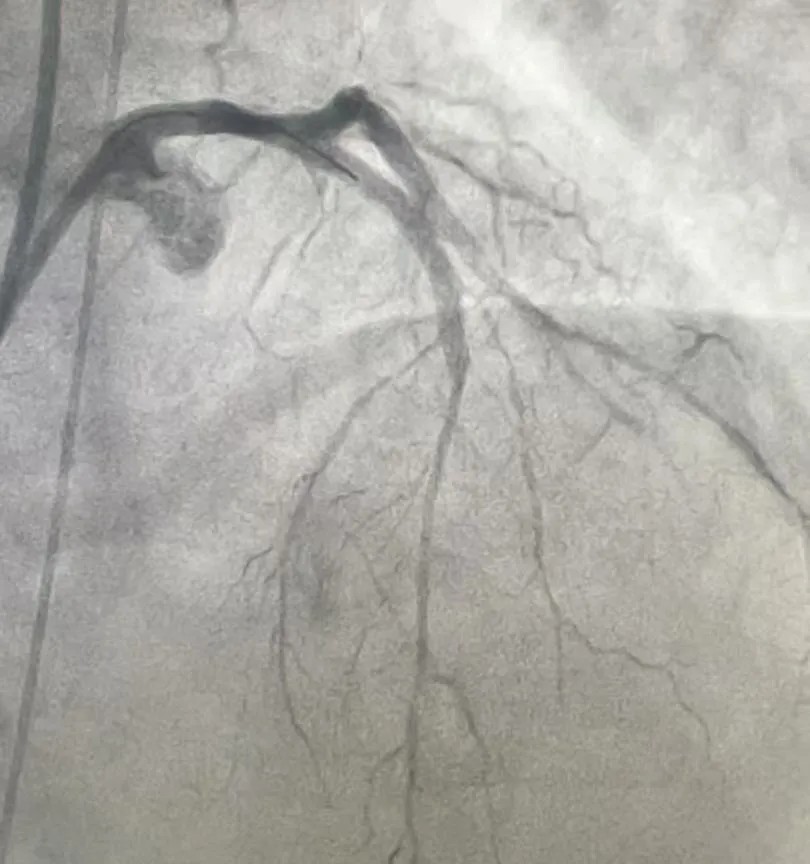

经过2小时的紧张奋战,前降支和回旋支成功开通,闭塞的血管重新“通车”,濒死的心肌迎来“救命血”。术中造影显示,支架贴壁良好,血流恢复至正常(TIMI3级),手术圆满成功。

(术后影像)